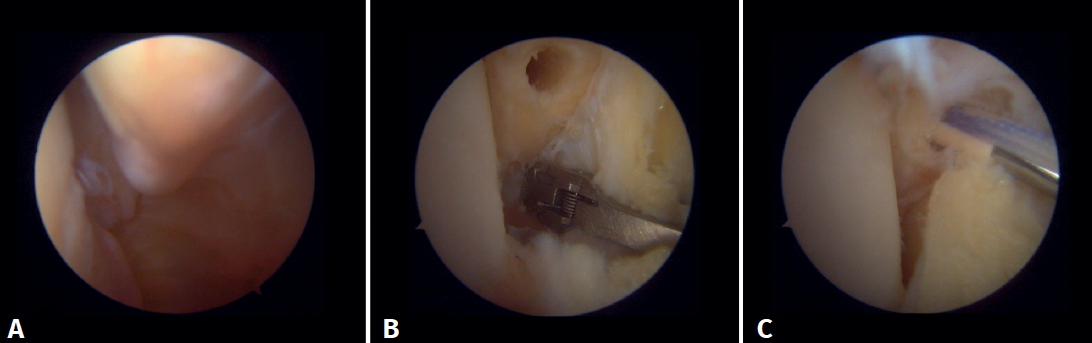

Evaluación artroscópica de la sindesmosis

Desde el portal anteromedial tenemos una visualización directa de las fibras distales del LTPA. Una desinserción de estas fibras no se traduce siempre en inestabilidad de la sindesmosis, pero nos obliga a comprobarlo. Los autores preferimos la evaluación del plano coronal de la sindesmosis. Introducimos el artroscopio en la articulación tibioastragalina dirigiendo la cámara hacia craneal. De este modo, tenemos una visión directa de la articulación tibioperonea distal. Entonces evaluamos la estabilidad intentando introducir el palpador en la articulación. Si es posible hacerlo, catalogamos la lesión de la sindesmosis como inestable (Figura 6A).

Evaluación artroscópica del ligamento deltoideo

Existen múltiples métodos para evaluar la inestabilidad del complejo medial; mediante los portales anteriores del tobillo es posible valorar la estabilidad del ligamento deltoideo en su plano principal de acción, correspondiente al plano coronal. Chun et al.(20) describió inestabilidad cuando es posible introducir un palpador artroscópico en el espacio medial tibioastragalino (Figura 6B). Vega et al.(21) describió que, en la mayoría de las lesiones, la porción más anterior del ligamento deltoideo está desprendida del maléolo medial, mientras que sus inserciones proximales permanecen íntegras. En esta situación se puede introducir el palpador artroscópico entre la pared medial del maléolo interno y las fibras profundas del deltoideo.

Figura 6. Maniobras para evidenciar inestabilidad ligamentosa. A: lesión de la sindesmosis que permite la introducción del palpador en la tibioperonea distal; B: lesión del deltoideo que permite la introducción del palpador en el espacio medial tibioastragalino.